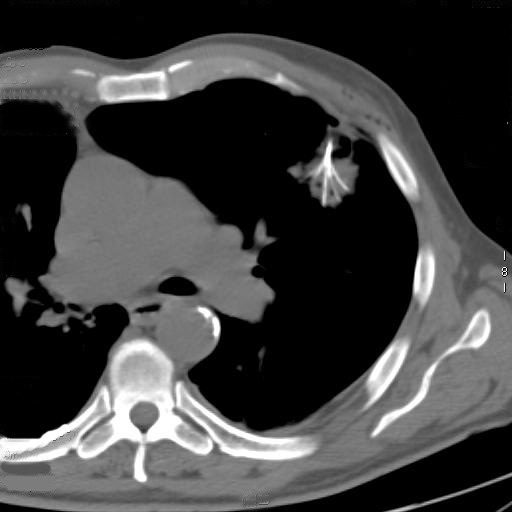

The procedure is performed with the patients under conscious sedation (Ketorolac 0.5-0.8 mg/kg, propofol 1-2 mg/kg/h, and remifentanil 0.1mg/kg/min) and local anesthesia (subcutaneous 1% xylocaine). Vital signs are continuously non-invasively monitored. CT guidance is employed in most of the cases; it is usually enhanced by the administration of contrast material before and after coagulation to obtain information about the real effectiveness of the procedure (Figure 3). In a selected group of patients with the tumour in contact with the thoracic wall, it is possible to work under ultrasound guidance (Video 2). The needle-electrode is inserted through an intercostal space after administration of local anaesthesia (Video 3). The correct placement is confirmed by CT (Figure 4) or ultrasound (Video 4) before applying the radiofrequency energy. The target temperature of ablation is 90°C. It is maintained for a time ranging from 15 to 27 minutes according to the size of the tumor; this variable also determines the gradual deployment of the electrodes, starting from 2 cm and then 1 cm for each step. When technically feasible, the ablation zone should include the whole lesion and one cm of the surrounding lung parenchyma.

Figure 4. A CT scan confirmed the correct placement of the needle with the deployment of the electrodes into the tumor.